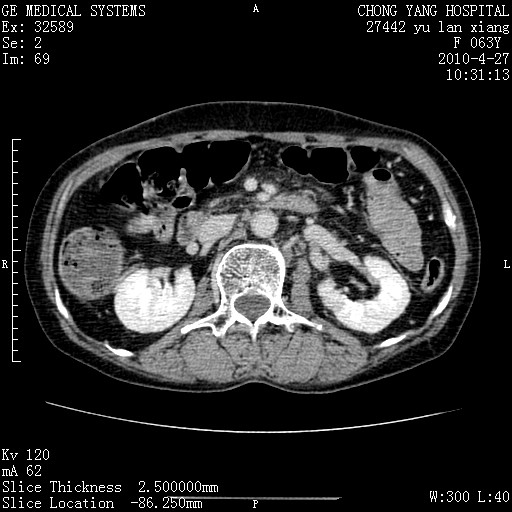

标题: CT26066:F63Y 上腹正中压痛半月,CA199:7400u/ml,MR示胰腺炎伴 [打印本页]

胰腺癌侵犯腹腔动脉干-分支、胃壁、左侧膈肌伴胰周及腹膜后淋巴结转移、胆囊切除术后。

胰腺癌侵犯腹腔动脉干-分支、胃壁、左侧膈肌伴胰周及腹膜后淋巴结转移、胆囊未显影。